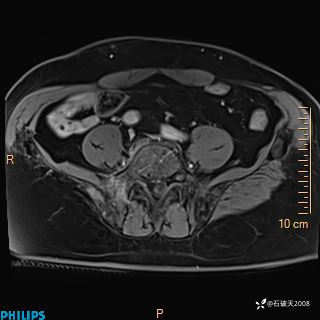

现病史:7个月前患者因骶尾部占位就诊于北京大学人民医院,MRI示:骶骨右侧及右骶前占位,考虑骨巨细胞瘤可能,动脉瘤样骨囊肿可能,神经源性肿瘤待排。行手术治疗,术后病理回示:XXXXX。术后给予对症治疗,具体不详,恢复良好。近几个月反复出现发热,伴骶尾部不适,多次住院给予对症治疗,2天前患者无明显诱因再次发热伴骶尾部不适,无大小便失禁,为求进一步治疗,遂门诊来我院,在门诊初步检查后,以“骶尾部肿物”为诊断收入我科。入院来患者神志清,精神一般,饮食睡眠可,大小便无明显异常,体重无下降。

2023年3月份MRI影像

增强轴位